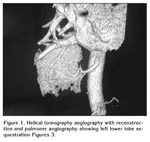

Multidetector CT was obtained after the administration of 2-4 mL/kg (maximum contrast doses 80 mL) non-ionic contrast agent with a concentration of 350/100 mg/dL (Iomeron 350, Bracco) via a subcutaneous antecubital vein at a rate of 3.5 mL/sec. Bolus tracking method was used. Acquisition was triggered automatically when the contrast reached the level of aorta. The images were sent to the workstation (Advantage Workstation, ADW 4.2, GE. Medical Systems). One of the patient?s multidetector CT angiography scan was? demonstrated Figure 1, 2.

Conventional transverse images, reformatted multiplanar reconstructions (MPR), maximum intensity projections (MIP), and volume-rendered 3D images were used. We confirmed the diagnosis of PS by digital substraction angiography (DSA). Helikal tomography angiography with reconstruction and pulmoner angiography showing left lower lobe sequestration Figures 3.